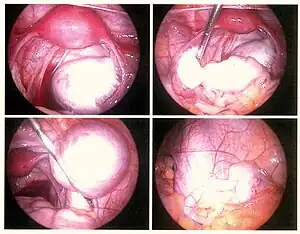

Laparoscopy

Laparoscopy, a surgical procedure where a camera is used to look inside the abdominal cavity, is the only way to officially diagnose the extent and severity of endometriosis.[73] Laparoscopy permits lesion visualization unless the lesion is visible externally (e.g., an endometriotic nodule in the vagina).[73] If the growths (lesions) are not visible, a biopsy may be taken to determine the diagnosis.[74] Surgery for diagnoses also allows for surgical treatment of endometriosis at the same time.

During a laparoscopic procedure lesions can appear dark blue, powder-burn black, red, white, yellow, brown or non-pigmented. Lesions vary in size.[75] Some within the pelvis walls may not be visible, as normal-appearing peritoneum of infertile women reveals endometriosis on biopsy in 6–13% of cases.[76] Early endometriosis typically occurs on the surfaces of organs in the pelvic and intra-abdominal areas.[75] Health care providers may call areas of endometriosis by different names, such as implants, lesions, or nodules. Larger lesions may be seen within the ovaries as endometriomas or "chocolate cysts", "chocolate" because they contain a thick brownish fluid, mostly old blood.[75]